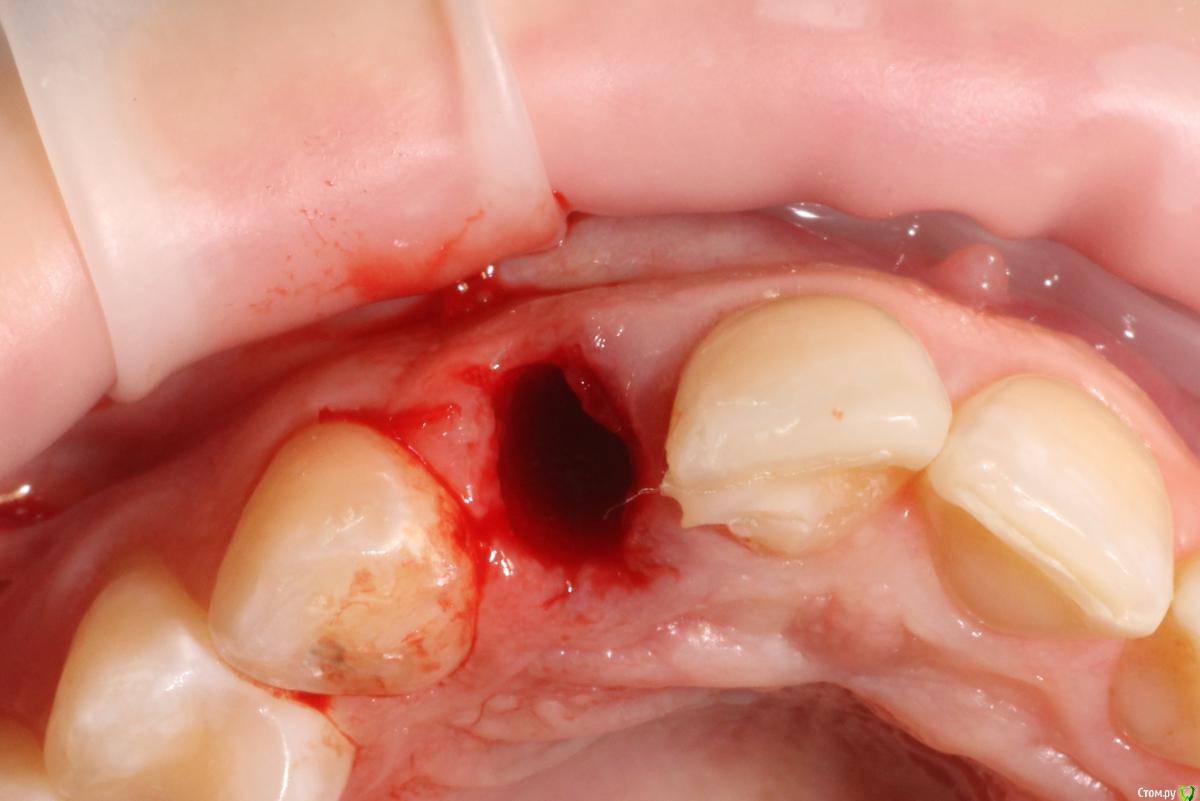

MenshikovDV Опубликовано 2 апреля, 2015 Поделиться Опубликовано 2 апреля, 2015 (изменено) Зуб 1.2 отлом коронковой части зуба, на период ожидания приема у хирурга и ортопеда (2 дня) приклеен к соседям. Вся процедура в одно посещение. Где-то часа два. Я ортопед, хирургия не моя, фото мои Изменено 2 апреля, 2015 пользователем MenshikovDV 19 Ссылка на комментарий

Aquarius Опубликовано 5 апреля, 2015 Поделиться Опубликовано 5 апреля, 2015 в такую дыру лучше что-нибудь кинуть, имхо. Ссылка на комментарий

Alexey Doc Опубликовано 5 апреля, 2015 Поделиться Опубликовано 5 апреля, 2015 Класс! Аккуратно сработали!Единственно, думаю что аугментации была бы желательна. Ссылка на комментарий